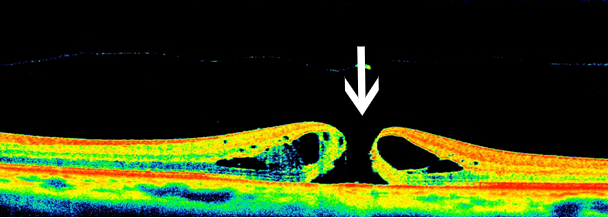

黄斑裂孔(全层)

眼科ab超检查单怎么看常见眼底疾病检查结果的秒懂解读_https://www.jmylbn.com_新闻资讯_第7张这个病就是老百姓说的“眼底有个眼儿”或“视网膜膜裂了”,其实就是指黄斑部视网膜的前9层发生的组织缺损,形成个小孔。

OCT:裂孔处无组织无光反射,呈黑色

图片来源:天津市眼科医院